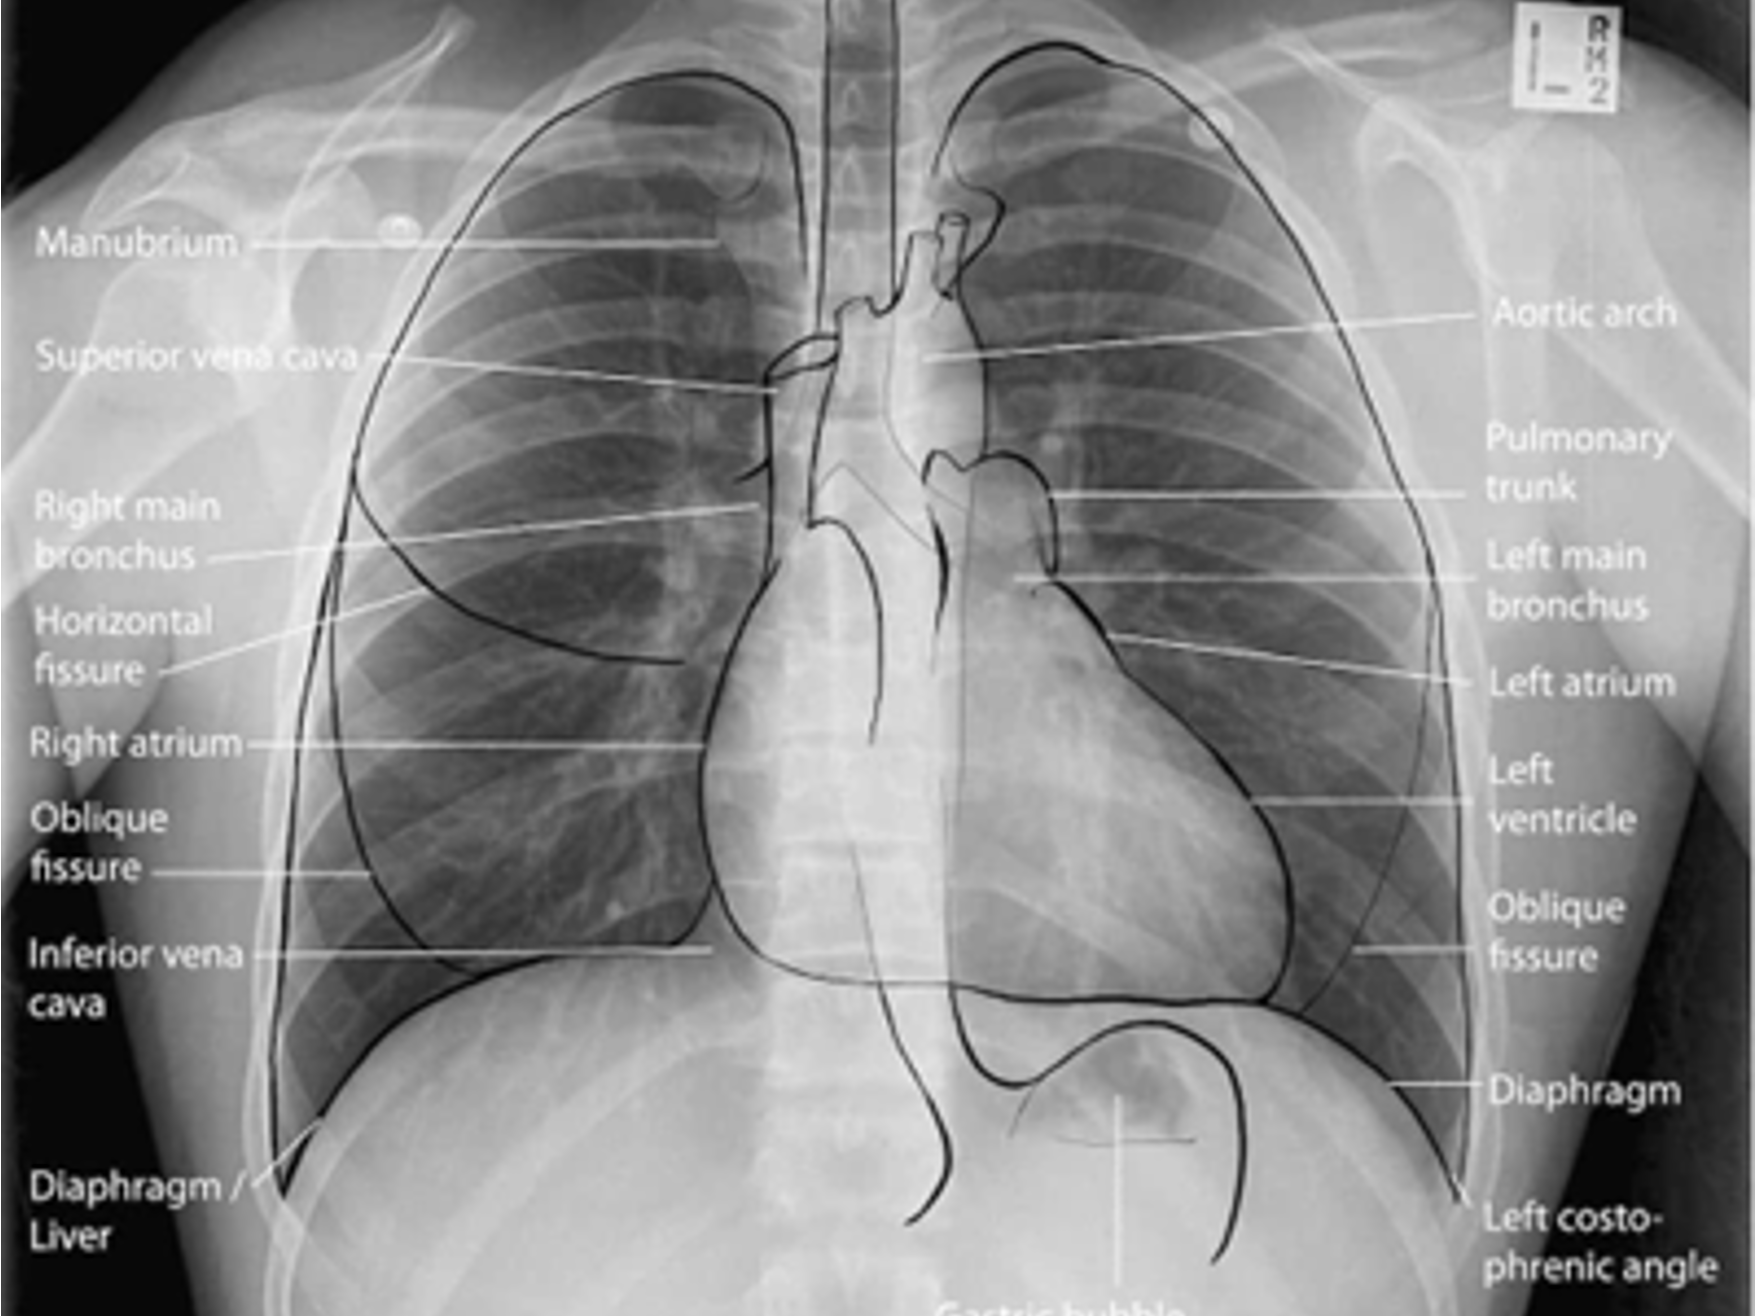

Normal CXR (PA & Lateral)

Name the mediastinal contours according to the numbers

1- superior vena cava

2- right atrium

3- inferior vena cava

4- aortic arch or knob

5- left pulmonary trunk

6- left pulmonary artery

7- left atrium

8- left ventricle

9- left cardiophrenic angle

Airway Structures on CXR

Name the structures according to number